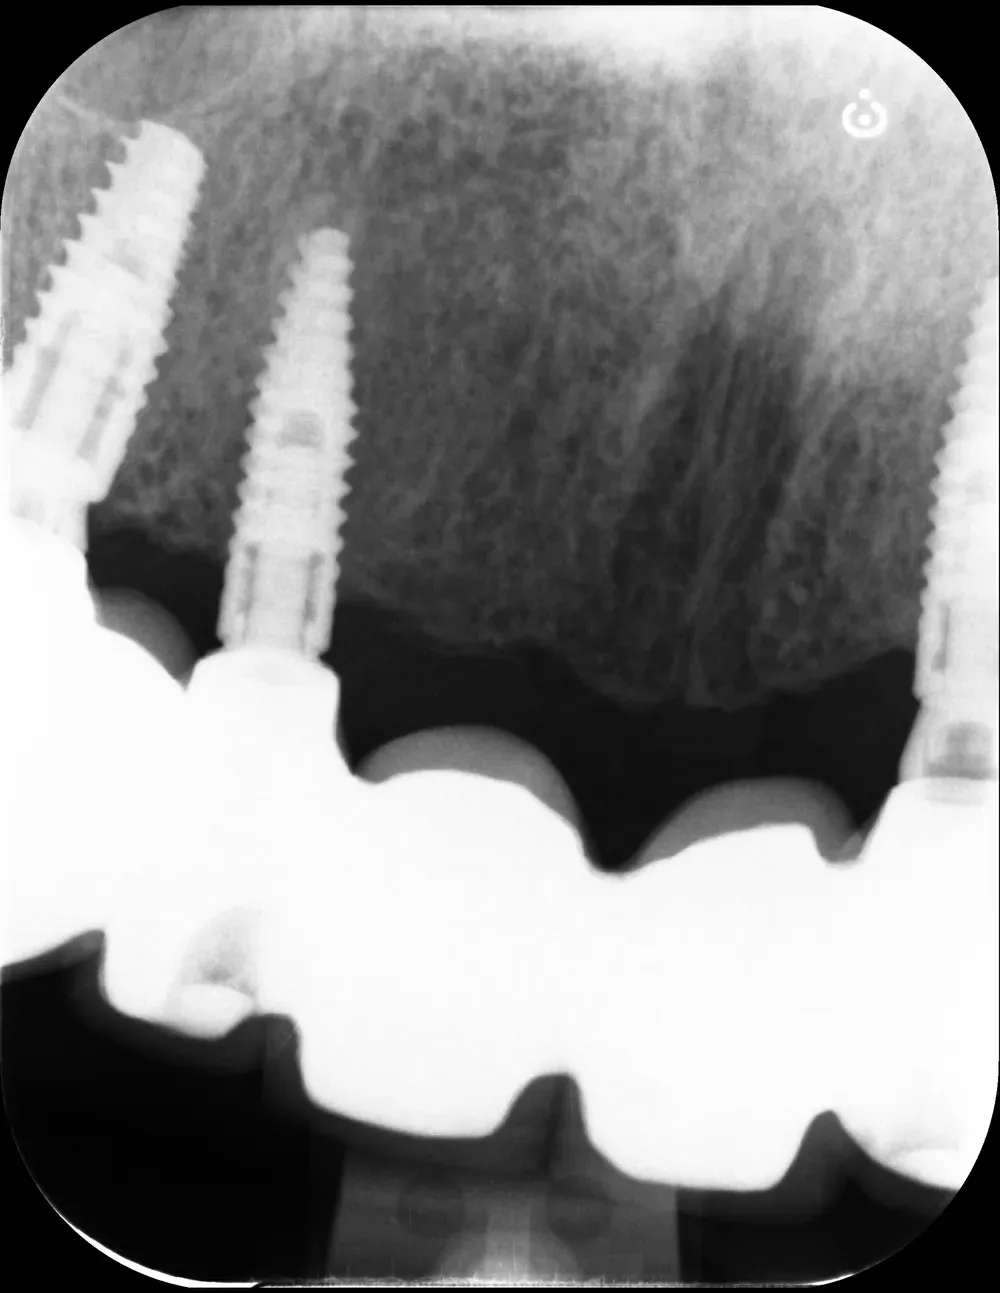

Il mascellare superiore destro era affetto da atrofia categoria S3 CCARD in posizione 16 e S2 CCARD in posizione 14 (precedentemente estratto), con presenza di cisti da ritenzione mucosa e setto di Underwood.

Inserimento impianti con rialzo del seno e aspirazione cisti da ritenzione mucosa del seno mascellare

Ho inserito due impianti, in posizione appunto 16 e 14, con minirialzo del seno mascellare e aspirazione della cisti da ritenzione mucosa tramite accesso laterale.

Al controllo radiografico, sette anni più tardi, gli impianti sono in ottima salute e perfettamente integrati (vedi immagini seguenti).